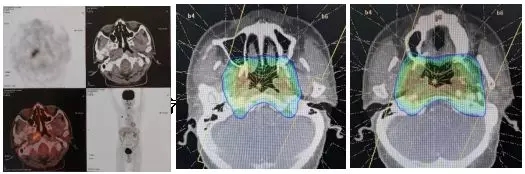

当时放疗医师勾画靶区时,参考了之前的PET-CT结果,将右侧鼻咽部高代谢病灶作为肿瘤靶区,从而有效避免邻近组织的不必要照射。体现了PET-CT协助放疗医师更精确的在细胞代谢水平上进行靶区勾画。患者进行12次放疗后,出现了严重的口腔粘膜反应,被迫停止放疗,并未完成根治剂量的照射。放疗后的影像评估显示:鼻咽部肿物明显减小,只是在粘膜上还有少许存在。之后患者没有再进行系统治疗,仅做了定期复查。直到2019年2月辗转至我院治疗。

图五:PET-CT指导放疗靶区勾画图